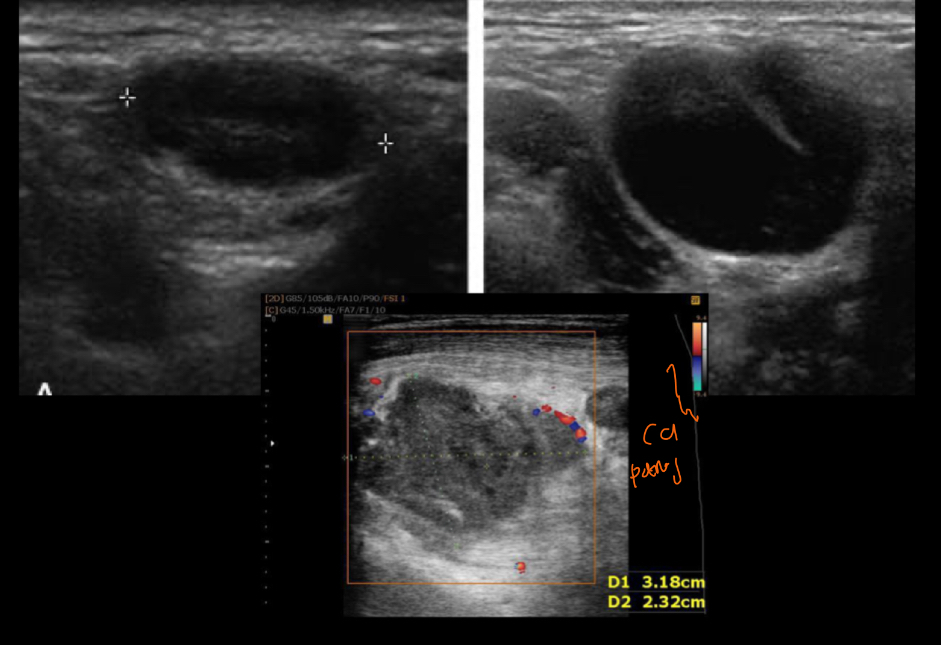

Q se ve en imagen

ganglio homogeneo hipoecoico

Mejor de imagen

us

Si es benigno q se vera

se preserva forma e hilio hiperecoico

si es maligno q tendria

perdida de morfologia